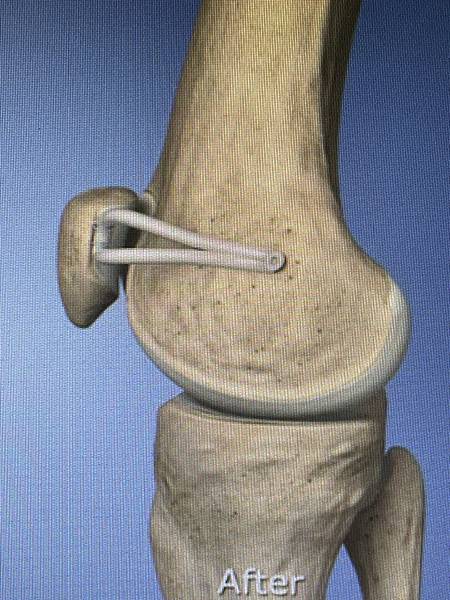

膝關節內側髕骨股骨韌帶重建示意圖